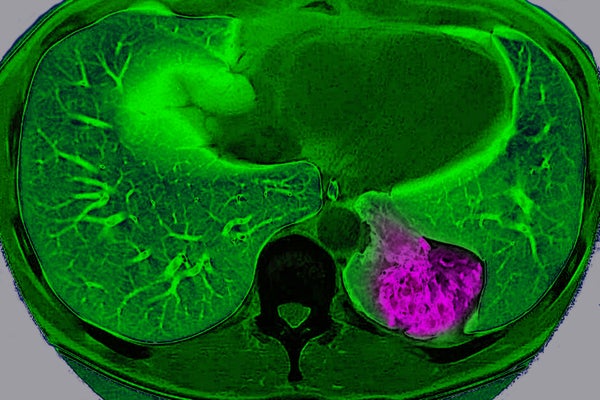

Lung cancer on the left pulmonary lobe, seen on a radial section MRI scan of the chest.

BSIP/Universal Images Group via Getty Images